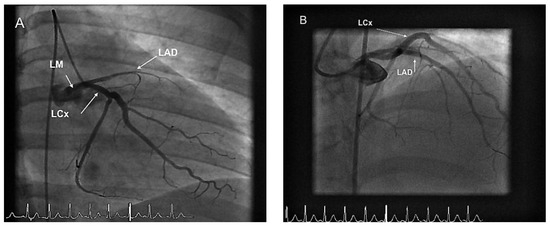

Acute Myocardial Infarction in a 19 Year-Old Woman: Sometimes Hoofbeats are Zebras

by Diego Arroyo, Tobias Rutz and Jean-Christophe Stauffer

We report the case of a 19 year-old woman who presented with chest pain at the emergency department. Cardiac risk factors were obesity, dyslipidemia, cigarette smoking and a sedentary lifestyle. Investigations revealed an acute myocardial infarction with ST-segment elevation. A thrombotic occlusion of [...] Read more.

We report the case of a 19 year-old woman who presented with chest pain at the emergency department. Cardiac risk factors were obesity, dyslipidemia, cigarette smoking and a sedentary lifestyle. Investigations revealed an acute myocardial infarction with ST-segment elevation. A thrombotic occlusion of the mid left anterior descending artery was visualised on coronary angiography, the cause of which remains unknown. Full article